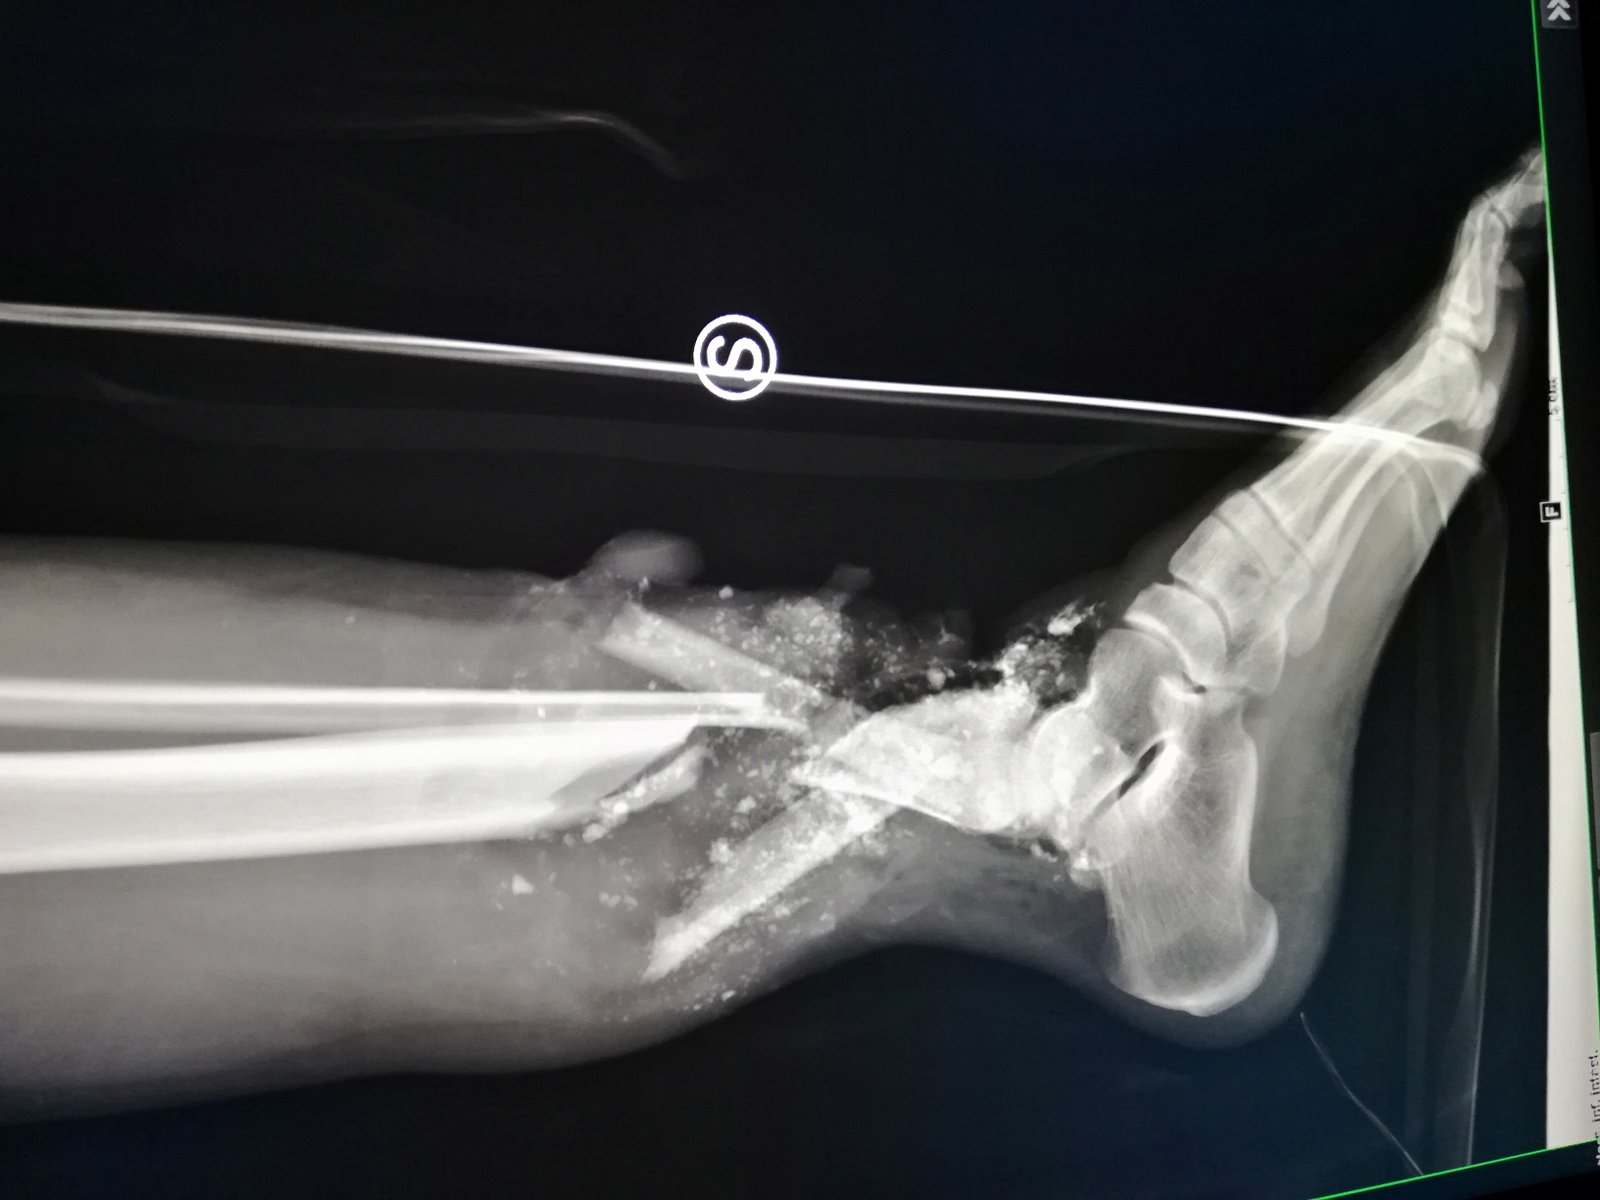

• Ortoplastica (arto inferiore)